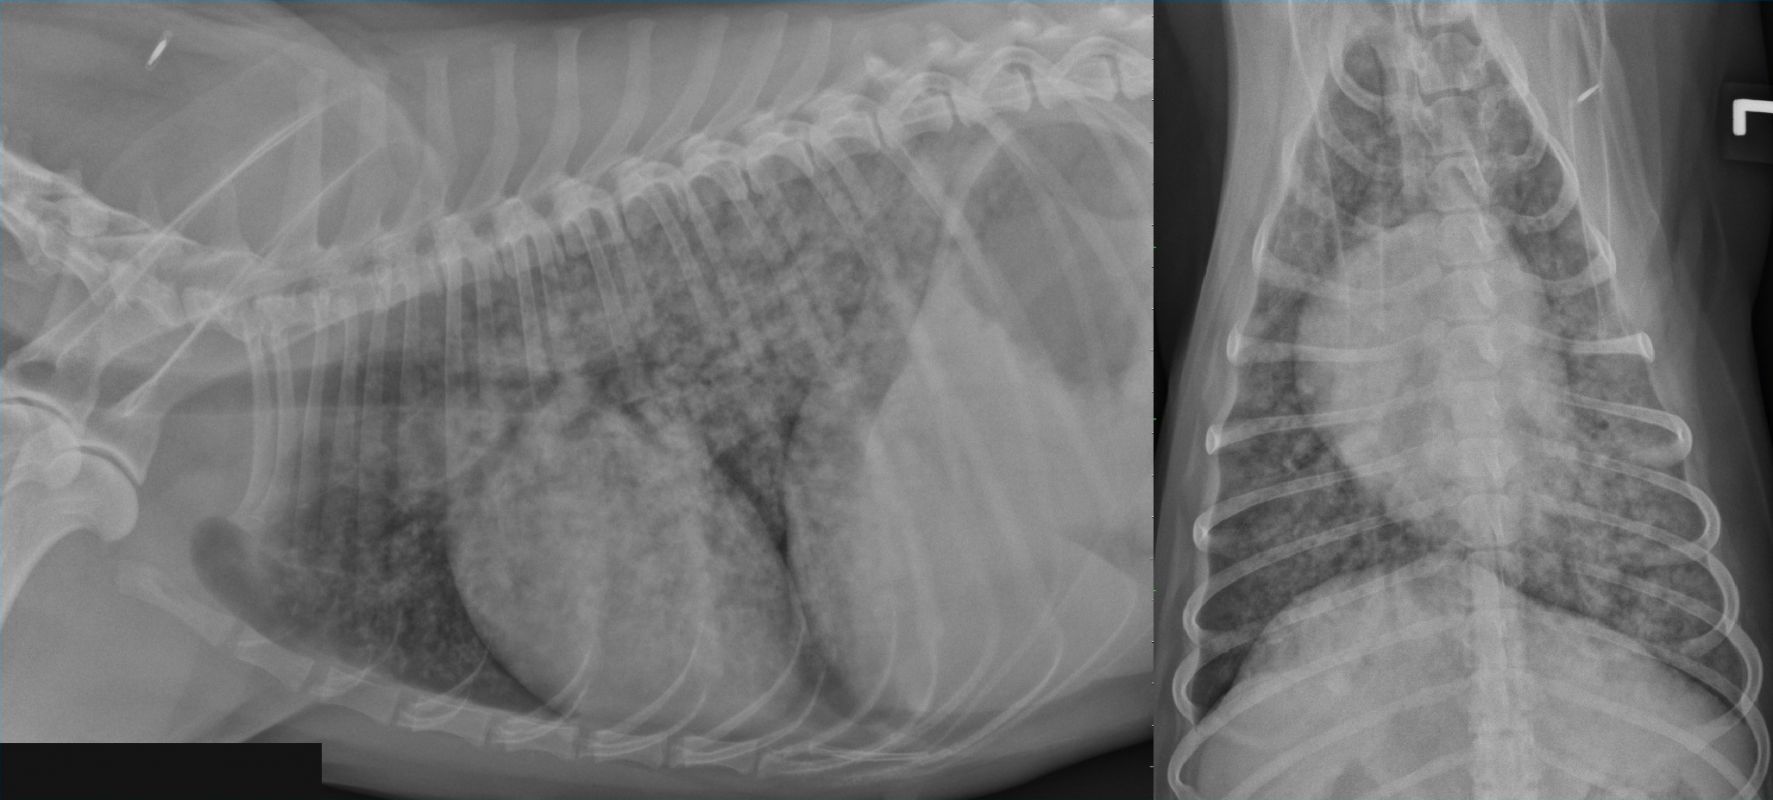

Normal Vd Abdominal Radiograph Dog Gdv Bloat Dog Ray Stomach Radiograph Dog Chest X Ray Normal Normal vhs for dogs = 8.4 to 10.5* normal vhs for cats is < 8.1. Vlas measures the la size on a right lateral projection. The following radiographs are of a dog’s chest. An enlarged heart is called cardiomegaly,. The first two normal ones are labeled so that you can see the problem in the two with the enlarged heart.. Dog Chest X Ray Normal.